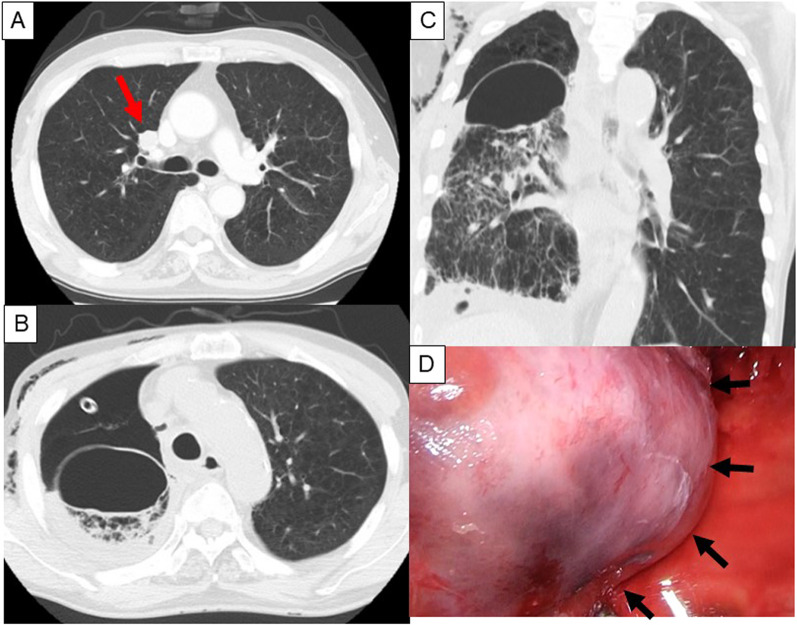

Fig. 3.

Preoperative CT and newly formed pulmonary cyst in Case 2. Preoperative CT shows a nodule measuring 16 mm in the right S3 (arrow) and severe emphysematous changes (A). Postoperative CT performed on POD 17 reveals newly developed pulmonary cyst at apex of S6 (axial section: B, coronal section: C). Broad-based pulmonary cyst with hole is recognized during reoperation (arrows) (D)

A man in his 70 s with COPD underwent right upper lobectomy with mediastinal lymph node dissection using multi-portal VATS for a right S3 nodule that was diagnosed as primary lung cancer (pathological stageIA2) (Fig. 3A). Smoking history was 52 pack-years. Preoperative PFT demonstrated FVC of 3193 mL (%FVC 120.6%) and FEV1.0% was 35.9%. CT revealed severe emphysematous changes. The interlobular planes between the upper and middle lobes, and between the upper and lower lobes, were divided using a stapler. Intraoperative sealing test revealed air leakage in S6 after interlobular dissection, which was sutured and covered with a PGA sheet and fibrin glue. Postoperative air leakage was observed and pleurodesis was repeated, resulting in decreased air leakage. However, massive air leakage was observed on POD 17. CT revealed a newly developed large pulmonary cyst at the apex of S6 (Fig. 3B, C). On POD 19, open thoracotomy was performed. The pulmonary cyst was observed at the apex of S6, and its location was different from that of the sutured part during the first surgery (Fig. 3D). Massive air leakage was observed in the pulmonary cyst hole. Blood clots and multiple air leakages were observed inside the cyst. The procedure was the same as that for Case 1. Postoperative course was uneventful. CT 1 year after surgery showed no development of a pulmonary cyst or air space.